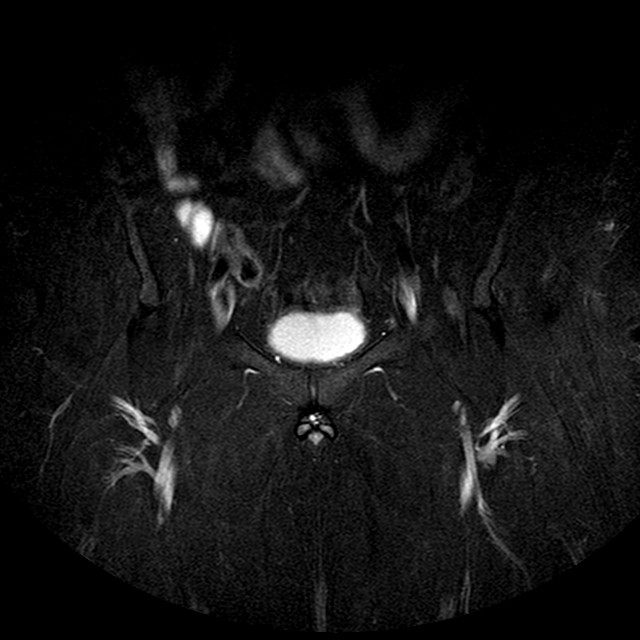

STIR

Evidenti e simmetriche alterazioni osteofitosiche in regione coxo femorale con riduzione delle rime articolari. Degenerazione completa del cercine glenoideo. Non attuali segni di versamento articolare. Non segni di edema osseo che escludono attuale algodistrofia od osteonecrosi. Lieve e simmetrica riduzione del trofismo della muscolatura glutea.